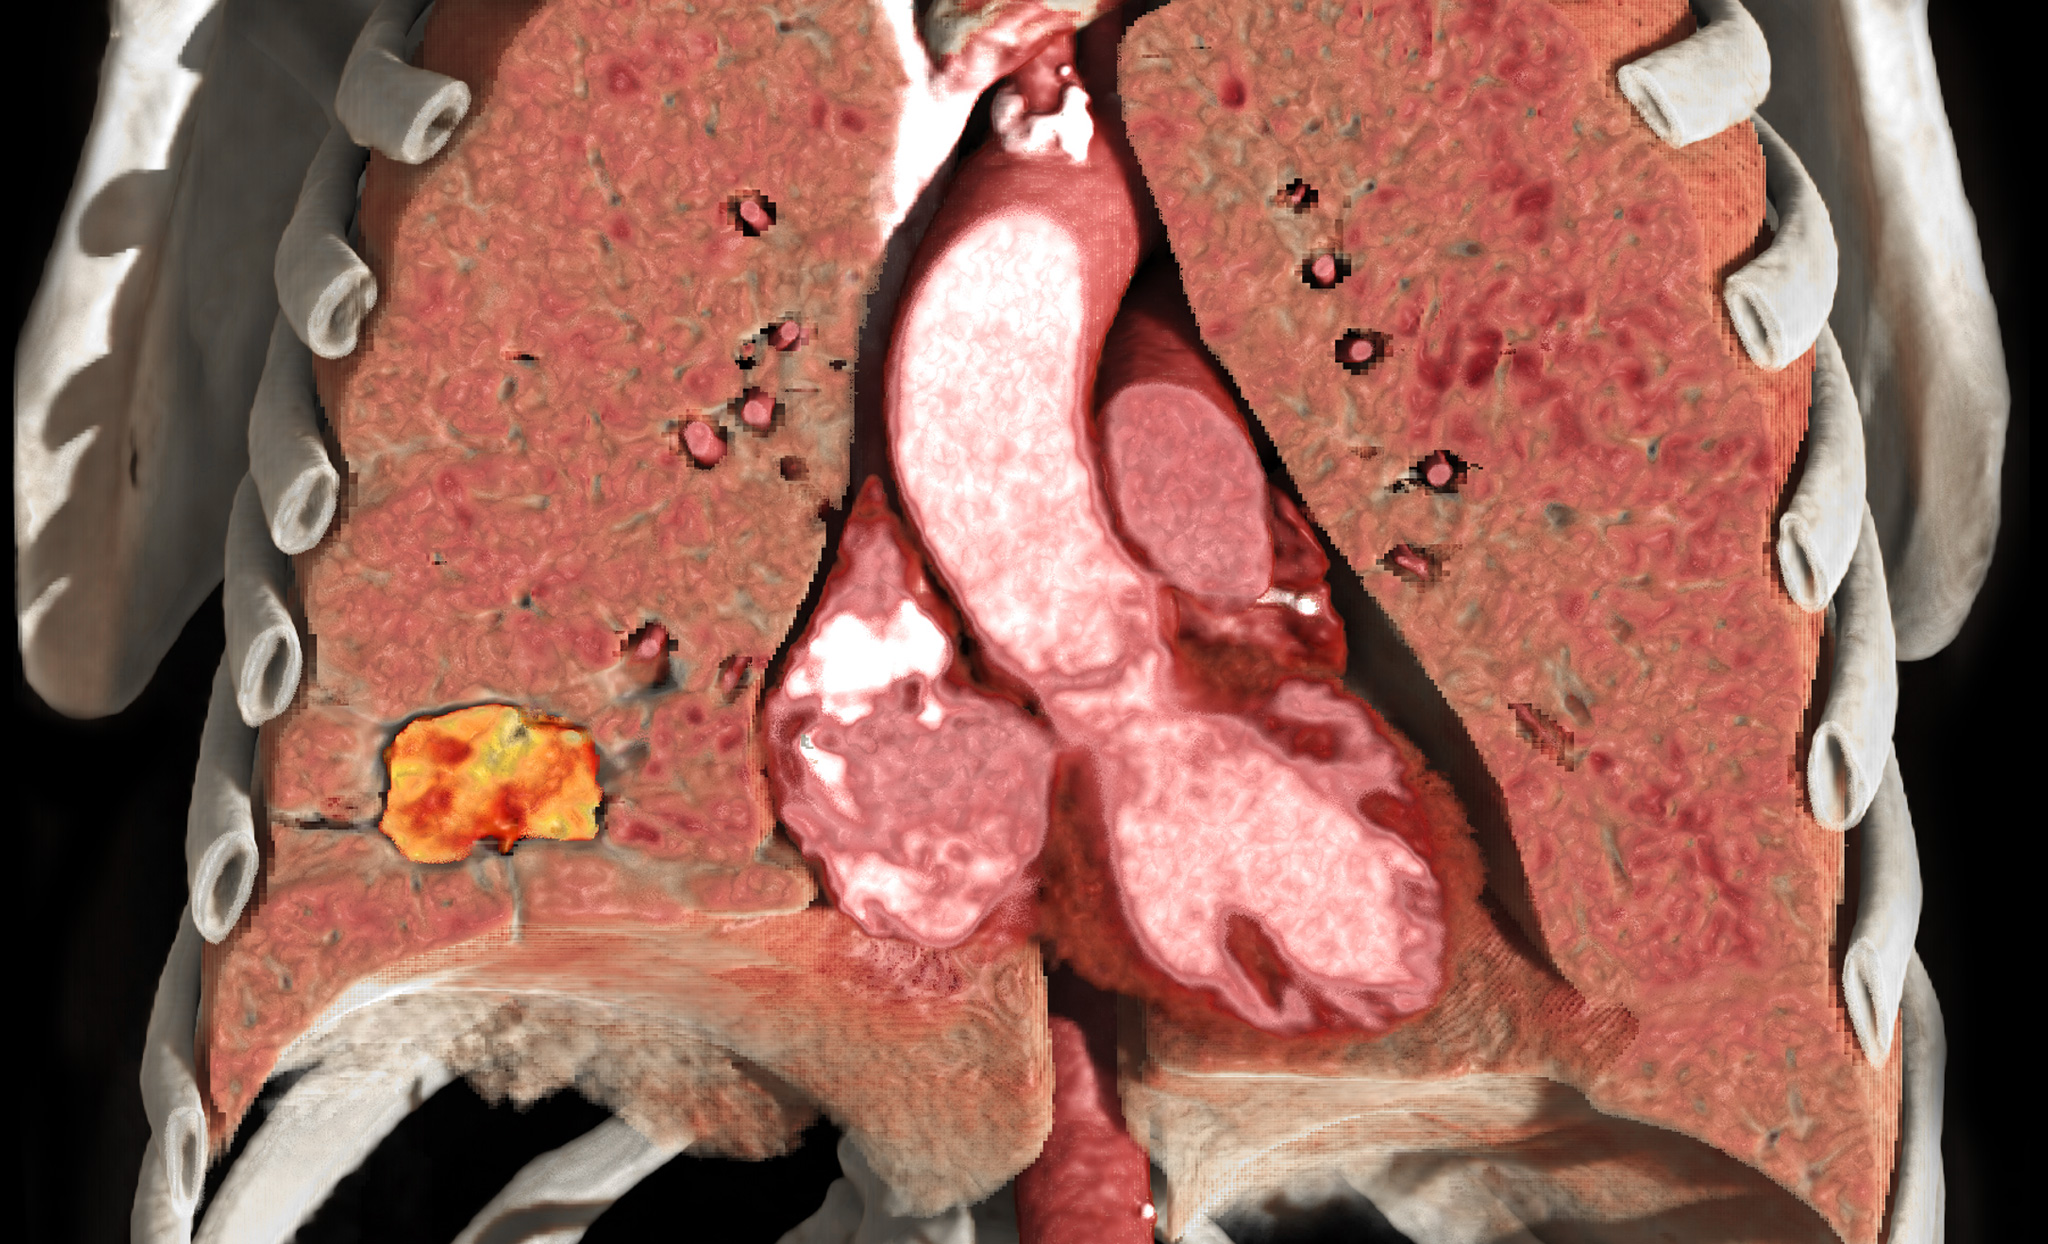

CT Lung Analysis

CT Lung Analysis aids in measuring and characterizing lung nodules. The interface and automated tools help to efficiently determine growth patterns and compose comparative reviews.

Visia™ CT Lung CAD

Visia™ CT Lung CAD is integrated into Vitrea® Advanced Visualization and facilitates time-efficient and safe radiological diagnosis of MSCT-images in clinical daily routine.